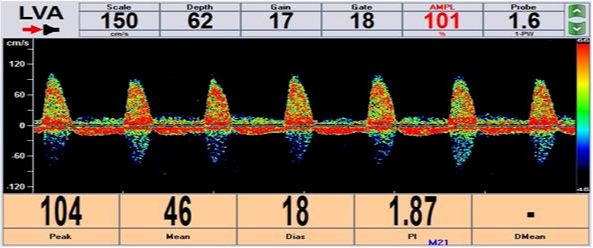

術前:

▲經顱多普勒超聲示左鎖骨下動脈重度狹窄時左側椎動脈血流完全反向

▲經顱多普勒超聲示:左側椎動脈血流形態恢復正常